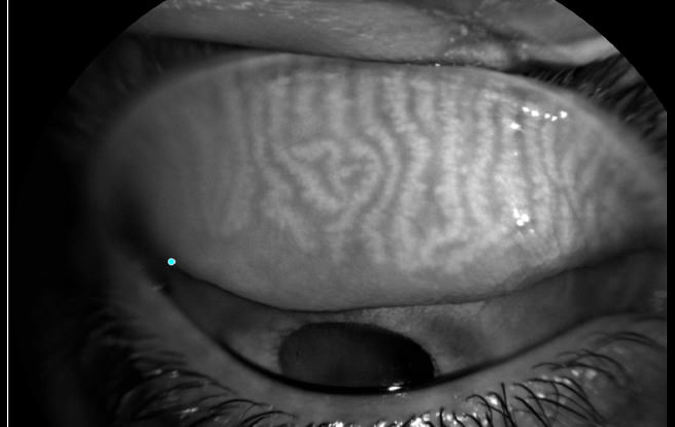

המחקר עסק בסוגיה עליה עדיין אין תשובה חד משמעית והיא האם יש קשר בין הרכבת עדשות מגע לבין בעיה בבלוטות המבומיאן MGD. בדקנו האם יש הבדל בחומרת MGD בין קבוצת מרכיבי עדשות מגע לבין קבוצת נבדקים שאינם מרכיבים עדשות ובחנו את הדירוג בעזרת שיטות אובייקטיביות וסובייקטיביות.